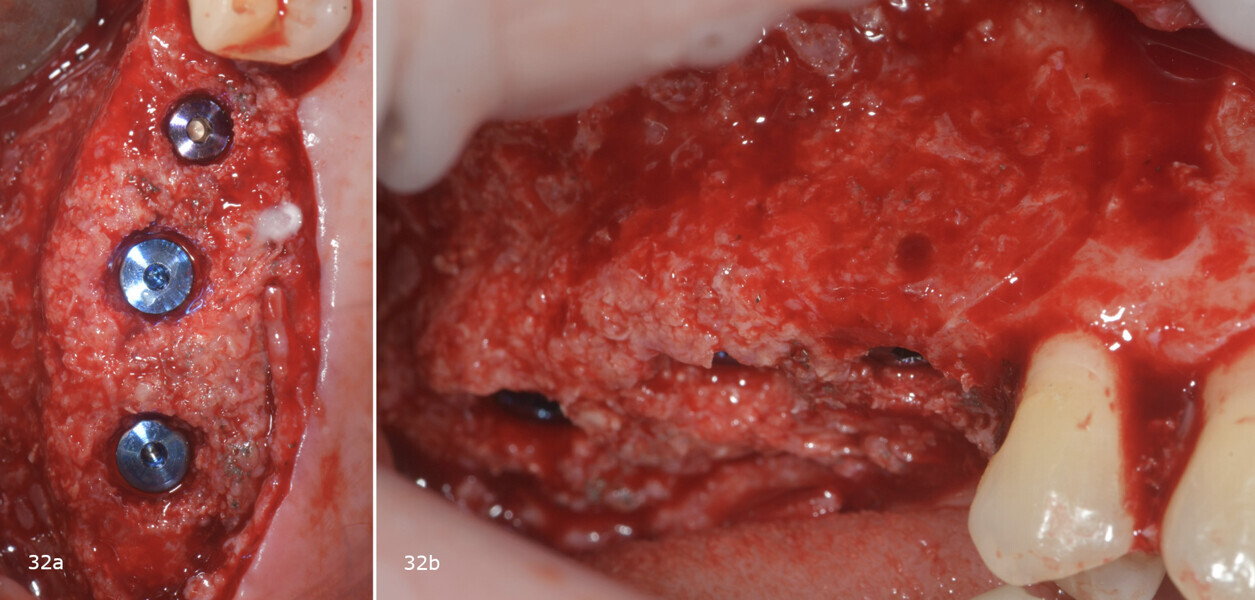

Subsequently, the surgical guide was placed and fixed in the planned position, the implant sites were prepared with progressive dedicated drills and three conical implants (T3, ZimVie) were placed in sites #15, 16 and 17 according to the prosthetically guided plan obtained from the guided surgery software (Figs. 29, 30a-c, 31a & b). The implants were covered to allow for proper osseointegration, and first intention closure was performed (Figs. 32a & b). After implant placement, a dental panoramic tomogram was taken (Fig. 33).